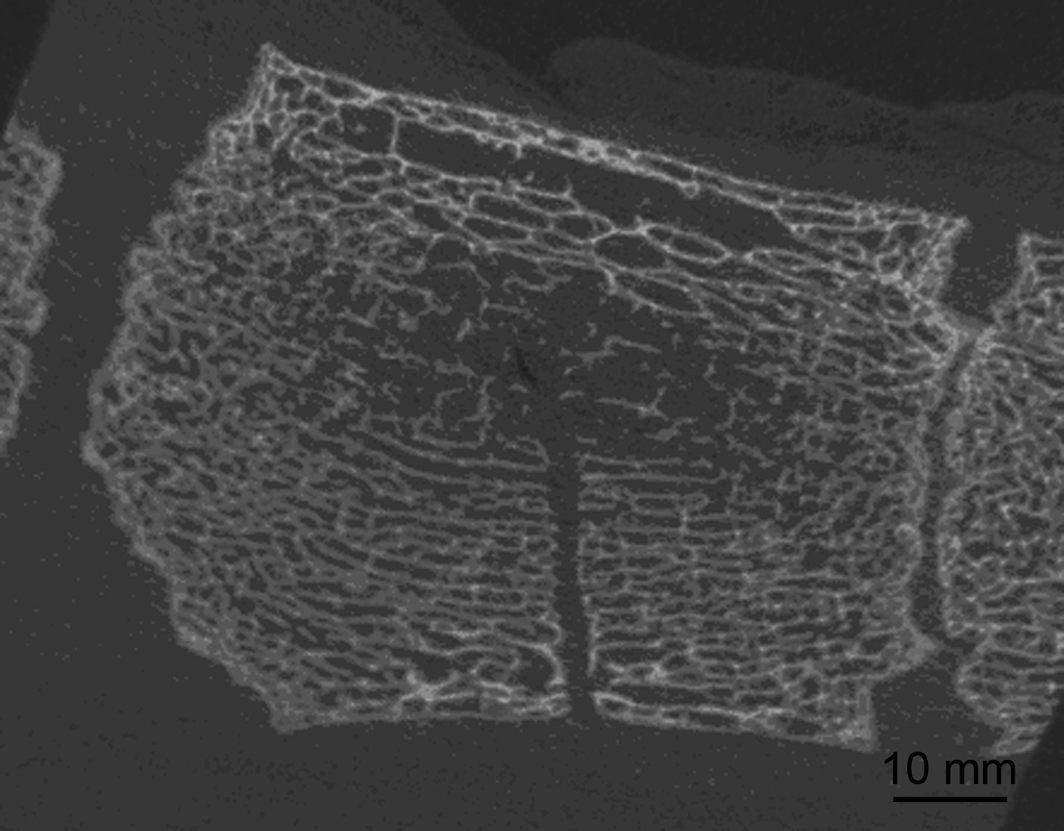

Figure 3.

Sternebra 5 after bone marrow aspiration. μCT image, longitudinal plane. The puncture canal within the bony, trabecular meshwork is clearly visible. No damage or fractures of the bony trabeculae are evident.

Measurements of sternebrae 4 and 5

The geometrical centres of the sternebrae were placed at 32.2 ± 3.3 mm (sternebra 4) and 27.3 ± 3.7 mm (sternebra 5) dorsal to the ventral bony margin of the sternebrae. In each sternebra, a centre zone composed of thin and loosely arranged bony trabeculae was visible in μCT images. This centre zone was always reached with the bone marrow aspiration canula when a 30 mm sternal insertion depth was intended (Fig. 3 and Fig. 4). The thickness of the ventral cartilage, measured on cCT images was 12.0 ± 5.0 mm (sternebra 4) and 6.6 ± 2.3 mm (sternebra 5). The μCT images always showed a clearly defined puncture canal (Fig. 3). The bony trabeculae lining the puncture canal did not present any signs of fractures or damage. The same applied for the area surrounding the dorsal end of the puncture canal, which was the supposed area of bone marrow aspiration (Fig. 3).

The analysed μCT data demonstrated that the insertion of the Jamshidi needle (10 or 30 mm) causes no significant destruction of the bony trabecular meshwork. This observation is consistent with results that demonstrated only minimal histological destruction of bony trabeculae after sternal bone marrow aspiration (Kasashima et al. 2011). However, although the bony structures remain largely intact after bone marrow aspiration it is unknown whether the microenvironment, relevant for the re-migration and homing of bone marrow stem cells, regenerates sufficiently.